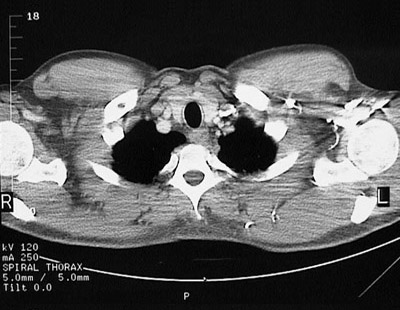

[T2] This is a normal chest CT scan demonstrating the right lung apex and left lung apex and pectoralis major muscle and sternocleidomastoid muscle and clavicle and internal jugular vein and internal carotid artery and right sublcavian artery and trachea and esophagus and scapula and head of humerus in the upper chest.